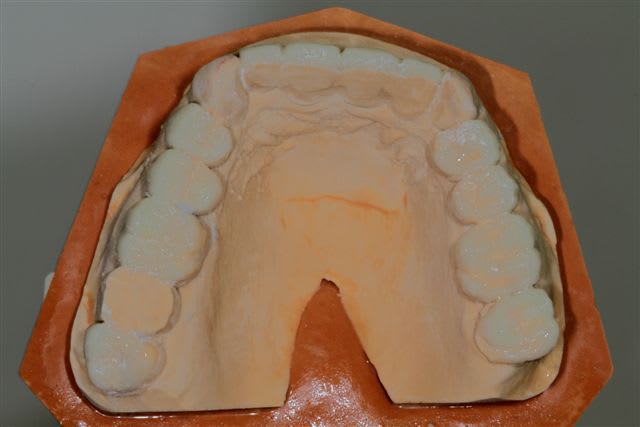

Il semble évident que ceci ne peut être traité que de façon globale, mais la difficulté est de le faire comprendre à la patiente, qui veut seulement un "sourire".

Donc dans un premier temps pano, pour bilan et empreintes pour essayer de lui faire comprendre l'étendue du problème.

premier wax up à minima

Mais autant un wax up ça nous parles, autant la patiente ne déclenche pas, et commence à douter.

La suite, les soins ont commencés le 07/08.

Postérieur bas (16/08)et haut (14/09) en place, essayage des Emax avec "cutback".